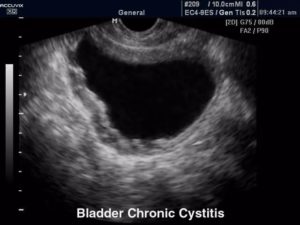

- При остром процессе сонография показывает признаки повышенной эхогенности, что свидетельствует о наличии воспалительных реакций. Осадок в моче пузырной полости выглядит в виде различных клеток и кристаллов солей. На начальном этапе развития цистита структура стенок органа остается ровной. Прогрессирование процесса вызывает развитие их ассиметричной формы.

- Хронический процесс при УЗИ отображается утолщением стенок мочевого пузыря и наличием осадочных хлопьев. При затяжном, хроническом течении процесса диагностируются наличие кровяных сгустков, прикрепленных к внутренним стенкам органа. На стадии процесса разжижения геморрагических сгустков их свертывание создает видимость неровных границ МП.

- Острый. При проведении исследования будет выявлено скопление высокоэхогенных частиц, что и говорит о наличии воспаления. Осадок содержит разнообразные клетки, а также солевые кристаллы. Изначально стенки будут ровными, а границы четкими, но при длительном течении картина меняется и орган приобретает асимметричную форму.

- Хронический. Исследуемый орган имеет утолщенные стенки, в их просветах имеется осадок, который определяется как хлопья. Если патология прогрессирует долго, могут быть сгустки крови, прикрепленные к стенке органа, что делает границы пузыря неровными.